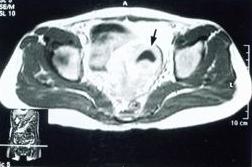

B型超聲、陰道鏡、腹腔鏡檢查、組織病理學檢查。

鑑別

1.子宮內膜異位症 子宮內膜異位症的痛經呈繼發性、進行性加重,若能觸及典型觸痛結節,有助於診斷。B型超聲檢查有助於鑑別。鑑別困難時應行腹腔鏡檢查。

2.卵巢囊腫 輸卵管卵巢囊腫需與卵巢囊腫鑑別。輸卵管卵巢囊腫除有盆腔炎病史外,腫塊呈臘腸形,囊壁較薄,周圍有粘連;而卵巢囊腫一般以圓形或橢圓形較多,周圍無粘連,活動自如。

3.卵巢癌附屬檔案炎性包塊與周圍粘連,不活動,有時易與卵巢癌相混淆,慢性炎性包塊多為囊性;而卵巢癌包塊多為實性,較硬,表面不規則,子宮直腸窩可捫及質硬的結節,常有腹水,患者一般情況較差,B型超聲檢查有助於鑑別。診斷有困難時,可藉助於腹腔鏡檢查或病理活體組織檢查。